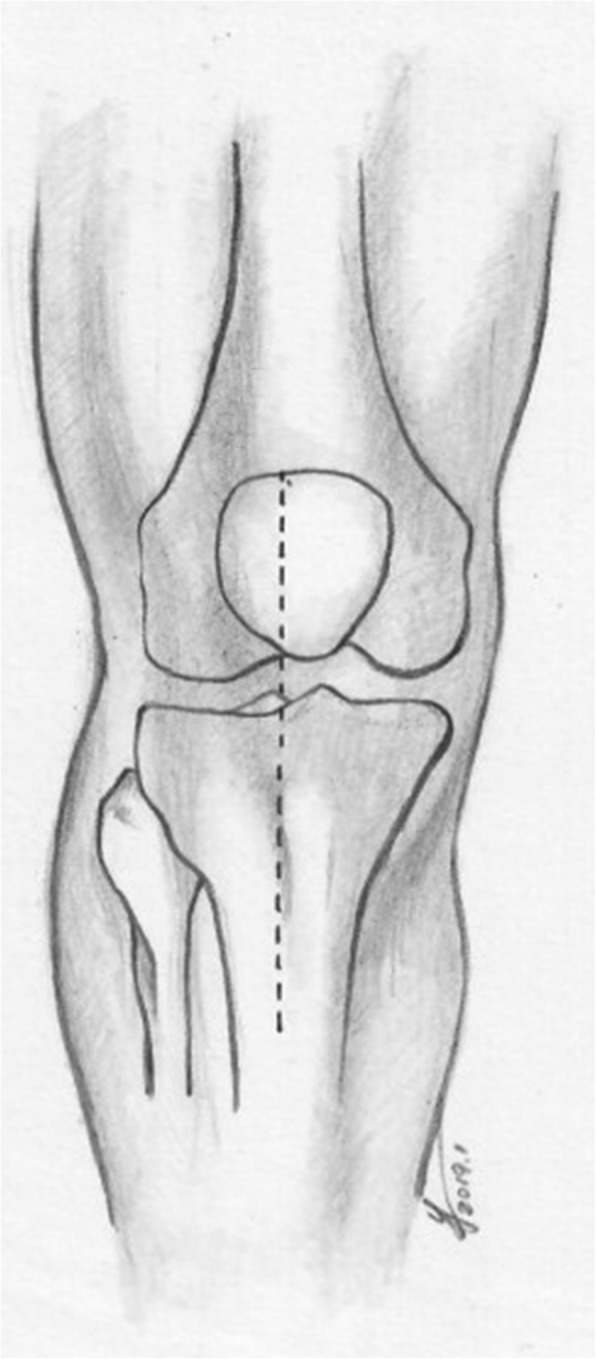

Fig. 1.

Modified anterior midline incision

Modified anterior midline incision (Figs. 1 and 2)

A longitudinal incision was performed parallel to the anterior midline of the knee, starting from the upper edge of the patellar, passing the lateral edge of the tibial tuberosity and approximately 1 cm lateral to the anterior tibial spine, and then extending approximately 7 cm distally. The full-thickness flap was protected, directly exposed to the deep fascia, stripped to both sides, and then exposed to the anterior edge of the fibular head laterally and the anterior edge of the superficial medial collateral ligament (MCL) medially. The flap was carefully retracted, and the lateral patellar retinaculum was incised, with a tibial tuberosity osteotomy performed occasionally to increase the anterior exposure, to obtain a 50–70-mm-long, 20-mm-wide proximal-end, 15-mm-wide distal end, and 10-mm-thick bone fragment in relation to its insertion in the tibial tubercle. The bone flap was then retracted proximally. Next, the anterior tibial muscle fascia was cut longitudinally, and the tibial is anterior muscle retracted laterally. A medial subperiosteal dissection was then used to reveal the medial fracture line. If the articular surface of the tibial plateau had a gap or step-off, the medial and lateral menisci were elevated to inspect the underlying joint surface. For restoration of sagittal plane alignment, disimpaction and elevation of the anterior metaphysis was performed by pulling the proximal metaphysis of the tibia forward and pulling the distal end of the tibia distally with the knee in the flexion position. The periosteal elevator was often used to reduce the collapsed fragments.